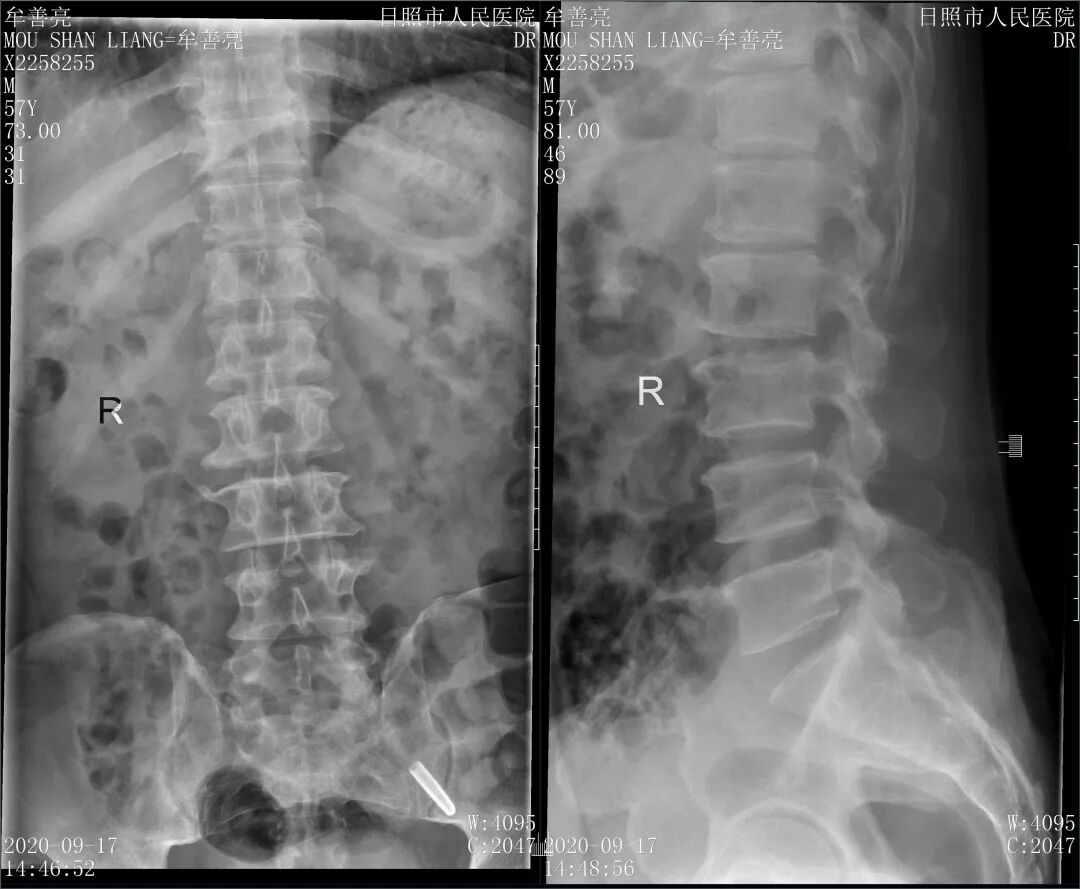

患者:牟**, 男, 57岁

主诉:腰痛伴左下肢放射痛3天。

查体:腰部及左侧椎旁压痛、叩击痛,伴左股部外侧放射痛,左下肢直腿抬高试验阳性(20°),左踇背伸肌力4-级,余肢体肌力、肌张力正常,血运、感觉良好。

影像学检查:腰椎MRI:

1、L4-5、L5-S1椎间盘突出

2、L2-3、L3-4椎间盘膨出

3、L5椎体后等信号,椎间盘组织脱垂可能

4、腰椎骨质增生

5、腰部皮下软组织局部轻度水肿

诊断:腰椎间盘突出症(左、L4/5)

腰椎椎管狭窄

术前影像资料

图1:术前影像

图2:术前影像